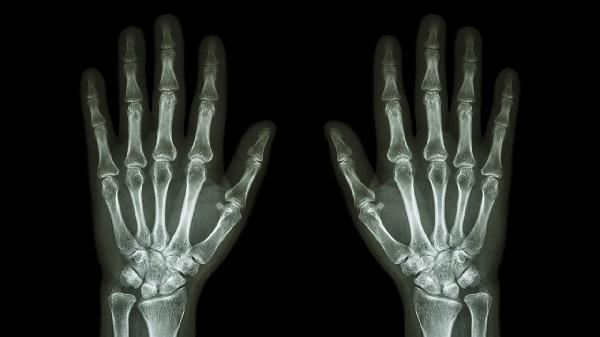

骨关节炎多见于40岁以上人群,晨起关节僵硬感明显,X线可见关节间隙狭窄。发病与年龄、肥胖、劳损相关。治疗需控制体重,减少爬楼梯等负重活动,可联合使用硫酸氨基葡萄糖胶囊、洛索洛芬钠片延缓软骨退化,疼痛严重时考虑关节腔注射玻璃酸钠。

外伤性疼痛有明显受伤史,可能伴随淤青、肿胀或畸形。轻微扭伤可通过冰敷、弹性绷带固定处理,疑似骨折需拍摄X线片,必要时石膏固定。恢复期避免提重物,可配合红外线理疗促进愈合。若存在肌腱断裂需手术修复。